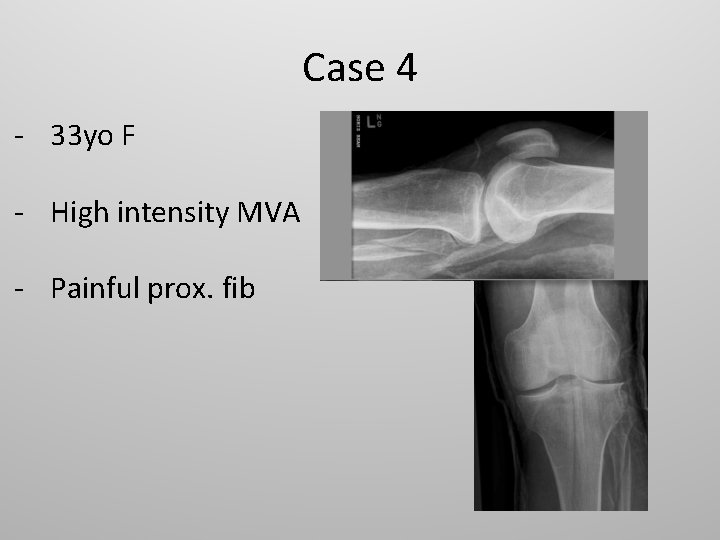

Case 4 - 33 yo F - High intensity MVA - Painful prox. fib